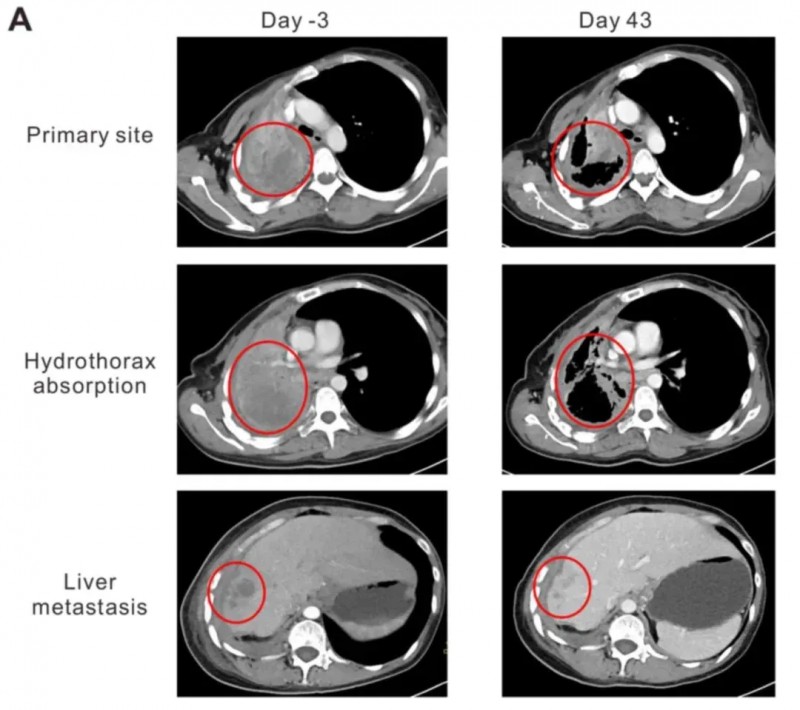

从化疗+靶向治疗失败到部分缓解!NY-ESO-1 TCR-T疗法让晚期肺癌绝境翻盘,43天实现肿瘤消退

NY-ESO-1是癌症免疫治疗中极具潜力的靶点,兼具良好的安全性与有效性,在11.8%-21%的非小细胞肺癌中均有表达。近期,知名期刊《Oncology Letters》报道了一则亮眼案例:通过NY-ESO-1特异性TCR-T细胞疗法治疗晚期非小细胞肺癌,成功使患者肿瘤明显缩小,达到部分缓解(PR)。

该案例患者为44岁女性,确诊为NY-ESO-1阳性晚期肺腺癌(LADC),且携带HLA-A2阳性与EGFR突变。此前她已接受多线治疗但均告失败:先完成6个周期的多西他赛联合卡铂化疗,疾病仍持续进展;后续尝试吉非替尼、厄洛替尼治疗,依旧无法控制病情。2015年9月随访CT显示,其右肺门、纵隔、右胸膜、右肝叶及肝包膜均出现疾病进展(PD),临床已无更合适的治疗方案。转机出现在右肺肿瘤支气管镜活检——标本免疫组化染色呈强NY-ESO-1阳性,这使她成功入组NY-ESO-1 TCR-T细胞治疗临床试验。

治疗效果远超预期:首次TCR-T细胞输注后第43天(2016年1月),CT扫描显示患者肺原发灶与肝转移灶均开始消退,胸水吸收且肺复张。具体数据为:肺原发灶从95×86×54mm缩小至64×44×54mm,肝转移灶从19.8×19.6×20mm缩小至10×10×10mm。依据RECIST 1.1标准评估,患者达到部分缓解(PR)。同时,她的卡氏功能状态评分(KPS)从治疗前的50分提升至90分,咯血、胸痛症状明显缓解,临床症状得到显著改善。

▲图源“Oncology Letters”,版权归原作者所有,如无意中侵犯了知识产权,请联系我们删除